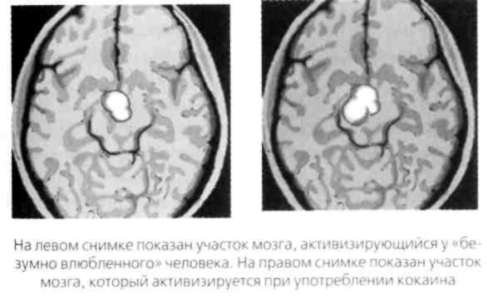

Во многих отношениях изменения в поведении во время романтической любви напоминают психоз. С биохимической точки зрения страстная любовь очень похожа на наркоманию. Доктор Джон Марсден, руководитель Британского национального центра зависимостей, выяснил, что любовь вызывает такую же сильную зависимость, как кокаин и скорость. Он считает романтическую любовь ловушкой, основная цель которой удержать партнеров вместе достаточно долго. Антрополог Хелен Фишер, автор книги «Анатомия любви», называет влюбленность «определенной последовательностью химических реакций, которые происходят в мозгу и напоминают психическое заболевание». Доктор Фишер считает, что во время влюбленности активизируются те же участки мозга, что и при употреблении кокаина, и человек испытывает то же сильное возбуждение, что и при приеме наркотиков. Исследователи также связали романтическую любовь с путями распространения допамина, гормона, отвечающего за ощущение эйфории, страстного желания и зависимости. МУРАШКИ БЕГУТ ПО СПИНЕ Химические вещества, которые вырабатываются в мозгу при возникновении новой любви, вызывают различные физические ощущения и реакции. Об этом говорят около 90% влюбленных. Люди теряют сон и аппетит, испытывают прилив крови к щекам, возбуждение, неловкость, эйфорию, ощущение мурашек, учащение дыхания и сердцебиения, головокружение, слабость в коленях, у них потеют ладони, они начинают заикаться. Многие из этих реакций связаны со страхом быть отвергнутым любимым человеком, так что все это является эволюционным блоком возбуждения и страха, испытываемых одновременно. Влюбленные не только испытывают эти эмоции, но еще и постоянно изучают лицо любимого человека, ища признаки взаимности. Кэрол Кинг идеально описала химические реакции, происходящие в процессе влюбленности, в тексте своей песни 1970 года «Я чувствую, как земля уходит из-под ног». Певица поет о том, как ее бросает из жара в холод, как она теряет эмоциональный контроль, как начинает стучать ее сердце, как небо падает, когда любимый рядом. Точно такие же ощущения испытывает любой наркоман. Любовь может стать восхитительным аттракционом, и такое случается неожиданно для большинства людей. Они не готовы контролировать свои чувства и не могут этого сделать. Эти ощущения возникают в части мозга, отвечающей за подсознание и первобытные инстинкты, — в коре. Эта часть гораздо сильнее рациональной, мыслящей части. Вот почему влюбленные ведут себя иррационально. Точно так же реакция «дерись или беги» заставляет человека при встрече со львом бежать сломя голову, а не спокойно и трезво обдумывать план спасения. Любовная эйфория вдохновляла поэтов и композиторов на создание лирических любовных песен, мелодий и трогательных стихов. А других та же самая любовь делала жертвами ревности и паранойи. Недавно проведенные исследования показывают, что любовь может кардинально улучшить здоровье человека, даже излечить рак и другие тяжелые болезни. Любовь заставляет нас продолжать жить с теми, чье поведение опасно для нашего благополучия, и такое случается довольно часто. ЕСТЬ НЕ МОГУ, СПАТЬ НЕ МОГУ Стадию влюбленности часто называют болезнью. Влюбленные говорят, что не могут есть, плохо спят. Они демонстрируют стандартное компульсивное поведение — например, звонят своим любимым по 20-30 раз в день. Такое поведение связано с низким уровнем серотонина и высоким уровнем окситоцина. Серотонин — это нейротрансмиттер, который повышает концентрацию, степень внимания и четкость восприятия окружающей обстановки и ощущение благополучия. Депрессия и пищевые расстройства также связаны с понижением уровня серотонина. Действие антидепрессантов как раз и направлено на повышение уровня этого вещества. В женском организме естественное содержания окситоцина на 30% выше, чем в мужском. Это явление в сочетании с низким уровнем серотонина объясняет, почему женщины чаще «сходят с ума» от своих партнеров и даже демонстрируют навязчивое поведение. «Любовь — это всего лишь грязный трюк, направленный на продолжение рода». У. Сомерсет Моэм В 2007 году Серж Брэнд и его коллеги из университетской психиатрической клиники в швейцарском Базеле опросили 1 13 человек в возрасте 17 лет. 65 из них сказали, что недавно влюбились. Брэнд выяснил, что влюбленные подростки меньше спят, чаще проявляют компульсивное поведение и обладают «массой безумных идей и творческой энергией». Влюбленные подростки более склонны к рискованному поведению — экстремальному вождению или банги-джампингу. Брэнд показал, что подростки на ранних стадиях интенсивной романтической любви ничем не отличаются от пациентов, страдающих гипоманией. Другими словами, иногда бывает трудно отличить влюбленного подростка от человека, которого со всеми на то основаниями считают психически больным. Если вы когда-нибудь говорили, что сходите с ума по кому-то, то были совершенно правы. ЧТО ПОКАЗЫВАЕТ СКАНИРОВАНИЕ МОЗГА Новые технологии, такие как ядерно-магнитный резонанс (ЯМР) и магнитно-энцефалографическое сканирование (МЭС), открыли перед учеными целый новый мир. Ученые получили возможность изучать работающий человеческий мозг, не причиняя вреда пациенту. Изучение любовных и сексуальных реакций мозга достигло пика в 2002 году, когда английские нейробиологи Андреас Бартельс и Семир Зеки из университетского колледжа Лондона провели исследование молодых мужчин и женщин, только что вступивших в новые отношения и «безумно влюбленных». Когда этим людям показывали фотографии их любимых, мозговая активность резко менялась в сравнении с тем, когда они смотрели на фотографии близких друзей. Сканирование мозга показало, что романтическое влечение активирует те зоны мозга, где сконцентрированы рецепторы допамина. Допамин, как вы помните, — это нейротрансмиттер, который влияет на ощущение наслаждения. Его часто называют «гормоном счастья». Высокий уровень допамина и норэпинефрина обостряет внимание, улучшает краткосрочную память, приводит к гиперактивности, бессоннице и целенаправленному поведению. Когда партнеры только влюбляются друг в друга, они часто демонстрируют признаки повышения уровня допамина: они полны сил, им не хочется спать и есть, они сосредоточены и находят огромное наслаждение в мельчайших деталях новых отношений. Бартельс и Зеки сравнили результаты сканирования мозга людей, находившихся в различных эмоциональных состояниях — сексуального возбуждения, ощущения счастья и кокаиновой эйфории. Оказалось, что результаты практически идентичны. ПРИДЕТСЯ ПРИЗНАТЬ: ВЫ — НАРКОМАН ЛЮБВИ Ниже показаны результаты сканирования мозга «безумно влюбленного» человека и кокаинового наркомана. Убедитесь, что они почти идентичны. ![]() Итак, влюблены ли вы или просто приняли наркотик, ваши ощущения будут одинаковыми. Сканирование также показывает, что у матерей, которые смотрят на своих младенцев, проявляется та же мозговая активность, что и у людей, глядящих на своих любимых. Бартельс и Зеки сделали вывод о том, что романтическая и материнская любовь связаны с продолжением рода, поскольку и любимый человек, и младенец обещают сохранение ДНК. |

Онлайн книга «Почему мужчины хотят секса, а женщины любви»